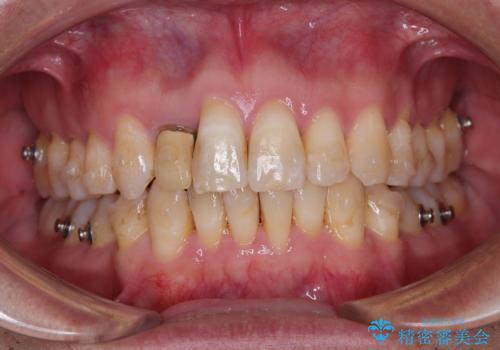

- 前歯のデコボコを気にして来院された患者様です。

目立たない装置で手軽に治したいとのことで、インビザラインにて矯正治療を行うこととしました。

前歯のクラウンは変色が著しいため、矯正治療後にオールセラミッククラウンにて補綴治療を行うこととしました。